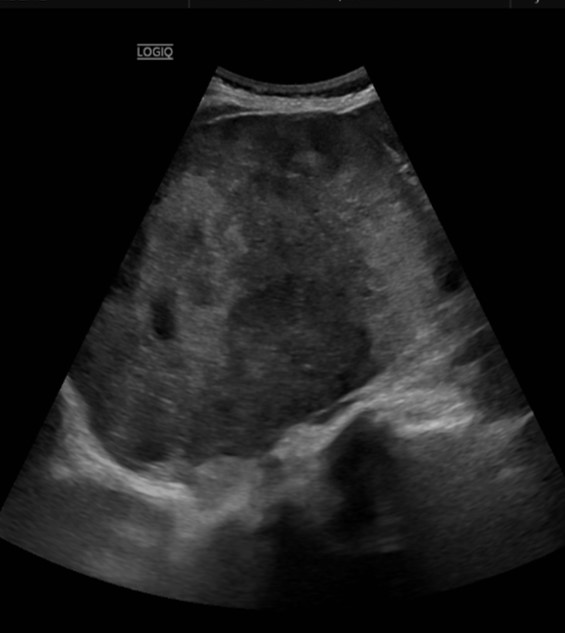

Mujer de 56 años consulta por dolor abdominal persistente durante el último mes, que asocia temporalmente con el final de las comidas navideñas. Además, menciona pérdida ponderal de aproximadamente 5 kg en los últimos dos meses y sensación de astenia constante.

Presenta un buen estado general, piel normocoloreada, normohidratada y adecuada perfusión. Las constantes vitales normales. La auscultación cardiopulmonar sin alteraciones. A la palpación abdominal, masa de gran tamaño en el flanco derecho, de consistencia dura, aproximadamente de 10 cm, con leve dolor a la presión. No hay signos de irritación peritoneal ni defensa. Extremidades inferiores libres de edemas o indicios de trombosis venosa profunda.

Tumor maligno de glándula suprarrenal.

Tras la evaluación clínica y las pruebas realizadas, la paciente fue remitida a urgencias para ingreso hospitalario y estudio. Allí se realizó una biopsia que confirmó el diagnóstico de carcinoma suprarrenal maligno en estadio IV. Se inició tratamiento con quimioterapia.